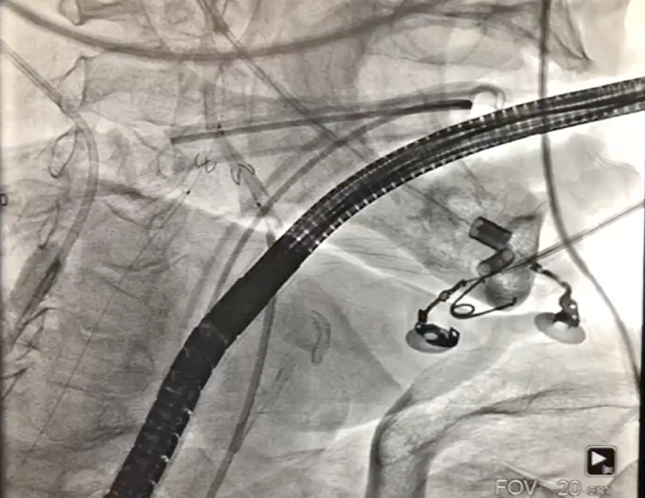

1、经右股动脉将Emboshield Nav6放栓塞装置输送至左、右颈内动脉。

主动脉根部造影示瓣膜位置合适(深度2 mm),轻度瓣周漏。遂释放瓣膜,撤回脑?;ぷ爸茫质踉猜晒?。

同时,TAVR术中脑?;ひ仓档霉刈?,可以有效的防治脑栓塞,能够改善患者生存及生活质量。